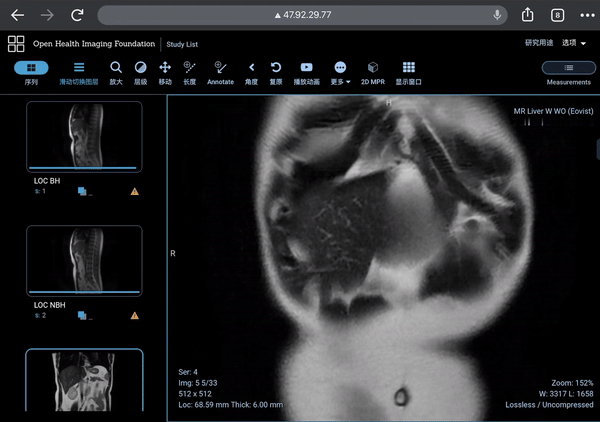

我使用的开源软件是社区中非常有名的Orthanc和OHIF viewer(Open Health Imaging Foundation)作为前后端。之后我实现了一个命令在云端部署这个容器组合。虽然目前一键,只能指的是一个命令,但可以随时扩展到真正的一键部署,一键消除。代码全部开源(https://github.com/yliu120/MedicalImageViewer),没有任何许可证,大家随拿随用。如果是对使用阿里云ECI部署感兴趣的同行,欢迎前来讨论。

下面自然是功能展示啦。用户可以自行上传影像数据(通过访问8042端口)。通常来说,目前的影像数据都是用DICOM这一种格式,无论X光,CT,核磁还是超声等等。从医院拿到的影像数据中基本都是这个格式的。上传这个过程只需做一次,因为数据会被写在独立管理的NFS数据卷中。在阿里云上关机重启,还会有之前上传的数据哦。(当然,数据卷也可随时自行删除)

上传完毕之后,就通过阿里云分配的公网IP浏览数据读片。OHIF viewer的体验非常丝滑。